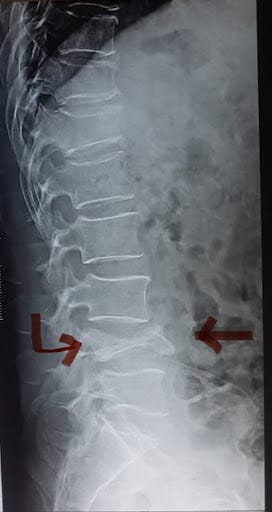

These are relatively common fractures in elderly individuals as the spine is one of the first bones to lose bone density and the mechanics of the spine is such that the lack of bone strength can often result in spine fractures even with little to no injuries to the spine. Hence, even the simplest of manoeuvres to a weak spine such as bending forward to pick up weight (without an actual history of falls or trauma to the body) can leave the spine most vulnerable to osteoporotic stress fractures. Similarly, in the case of falls/ injuries, the loading weight on the spine in addition to the force of injury that the individual's spine is susceptible to can result in compression fractures.

Cause of injuries:

• Injuries to the spine such as fall in a sitting position, or high-velocity injuries such as road traffic accidents and fall from height injuries.

• In the cases of severely weakened bones. Bending forward for prolonged periods when the spinal bone (vertebra is too weak to handle such a manoeuvre)

Non-operative management for simple wedge compression fractures which have retained significant height even after the compression and do not pose a threat to the spinal cord or risk of progressive spinal deformity.

In case of stable spine fractures which pose no threat to the spinal cord but cause severe prolonged pain of the back, an alternative minimally invasive option of treatment involves a day care procedure known as Vertebroplasty or kyphoplasty under local Anaesthesia.